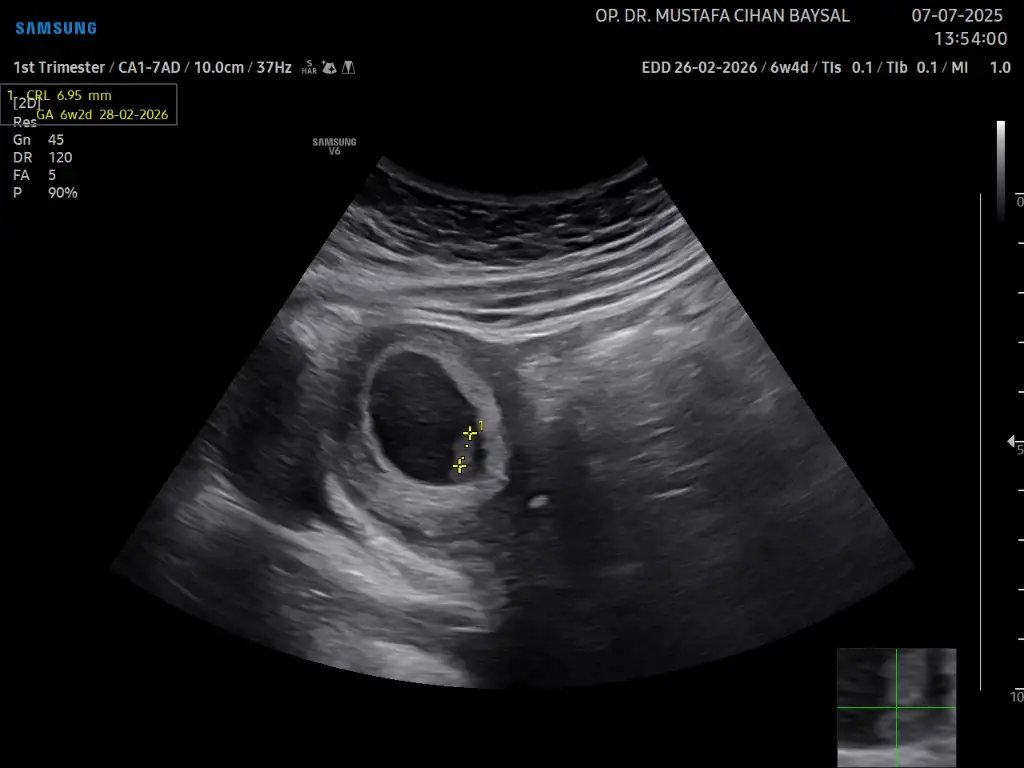

6 hafta 4 günlük hamileyim keseye göre cinsiyet tahmin edebilecek arkadaşımız var mı ultrason görüntüleri karından çekildi.

Eklentiler

• IMG_4570.webp

24,4 KB · Görüntüleme: 82

24,4 KB · Görüntüleme: 76

• IMG_4569.webp

31,4 KB · Görüntüleme: 73